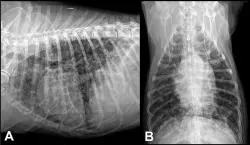

Figure 2: Right lateral (A) and ventrodorsal (B) radiographic projections of the thorax of a dog presenting for progressive coughing and acute dyspnea. A diffuse structured interstitial lung pattern is present. Primary differentials would include metastatic neoplasia and fungal disease.

Pulmonary parenchymal disorders, such as pneumonia (Figure 1), edema (cardiogenic or noncardiogenic), pulmonary contusions, interstitial lung disease, and neoplastic or fungal infiltration (Figure 2), can lead to both inspiratory and expiratory difficulty. The presence of heart murmurs, gallops, or arrhythmias may suggest underlying heart disease but not necessarily congestive heart failure.